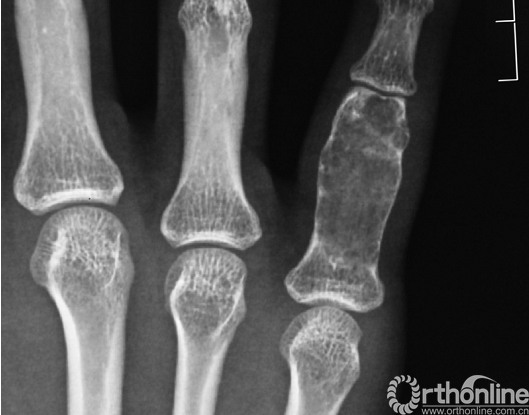

影像学特点:在X线上的典型表现为干骺端的部分溶骨性病变。具体表现为由弧形、螺旋形和斑片状组成的特征性的软骨钙化图案(图5)。手部的内生软骨瘤常发生于趾骨的近端和掌骨的远端。在X线上,钙化不明显,但可见皮质的明显扩张和变薄,与长管状骨形成鲜明对比(图6)。MRI的T2像明显高信号,这与软骨含水量丰富有关。若存在低T1和T2信号的散在区域,则提示为软骨钙化区。

图6.小骨中的骨软骨瘤,在手和足的短管状骨中主要表现为皮质变薄和扩张,而不能发现基质中的钙化。